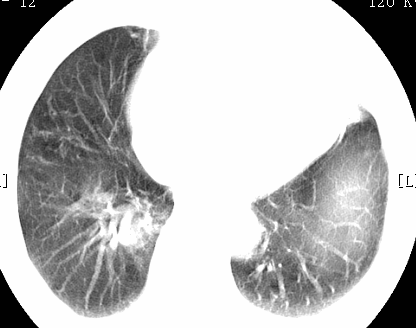

标题: CT26680:肺部右下肺静脉干结节的界定 [打印本页]

标题: CT26680:肺部右下肺静脉干结节的界定

经追查说有支扩咯血病史,但不确定

考虑1、周围型肺癌,2肺静脉畸形,前者可能大,建议增强检查。

考虑1、周围型肺癌,2肺静脉畸形,前者可能大,建议增强检查。支持!

不排除右肺下叶周围型肺癌可能。